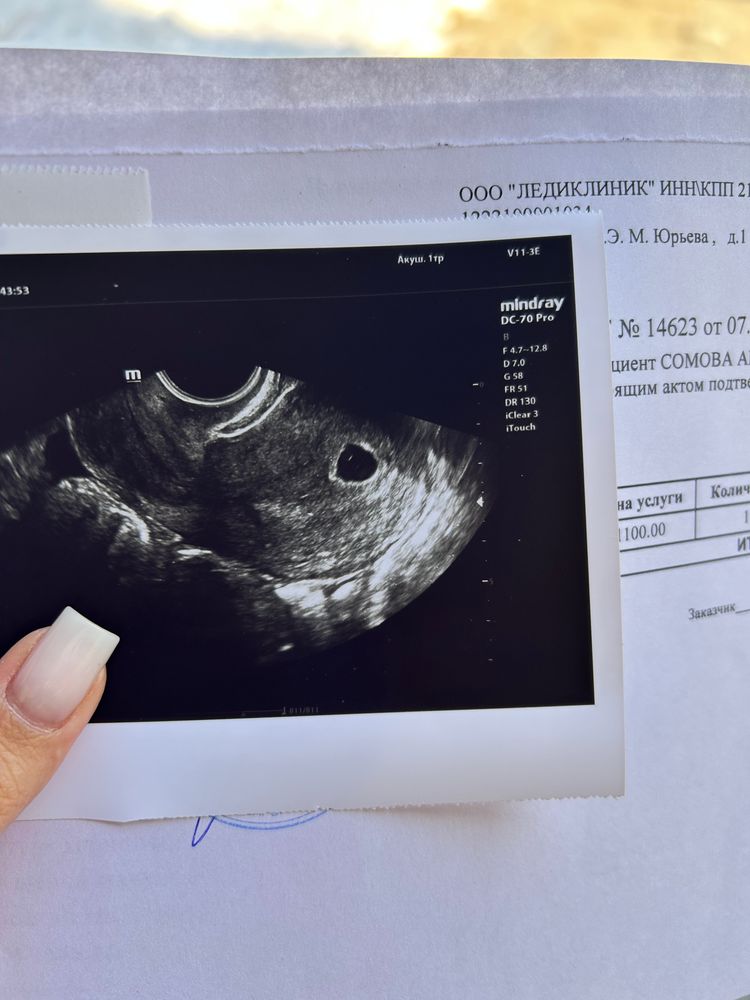

итак, сегодня ровно 6 недель по месячным, овуляция была на 17дц, и сегодня иду на узи.

Аня Борисова, я видела ваше узи,у вас пя примерно и соответстветствуеи 5,4 -5,5 акушерским,а не ровно 5 как в заключении,в 5 недель пя 5-7 мм, я думаю через неделю все будет уже,но можно и две

Татьяна, соответствует сроку 5 недель, скорее из-за поздней овуляции